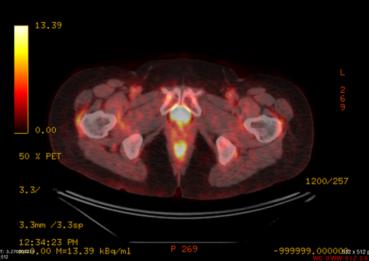

Rahim Ağzı Kanseri Tanı Yöntemleri Rahim Ağzı Kanseri Tanı Yöntemleri Rahim Ağzı Kanseri Tanı Yöntemleri Aşağıdaki durumlarda ...

Serviks (Rahim Ağzı) Kanseri Güncel Evrelemesi Serviks (Rahim Ağzı) Kanseri Güncel Evrelemesi SERVİKS KANSERİ EVRELEMESİ Evre 0 Anormal ...